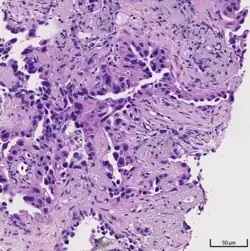

Histopathology

If possible, a biopsy of any suspected lung tumor is performed to make a microscopic evaluation of the cells involved and is ultimately required to confirm diagnosis.[7] Biopsy should be attempted in distant lesions first to establish a histologic diagnosis and to simultaneously confirm metastatic staging. The biopsy material is also used to analyze whether the tumor express any specific mutations suitable for targeted therapy (e.g. EGFR mutation or ALK mutation). Biopsy can be accomplished via bronchoscopy, transthoracic needle biopsy, and video-assisted thorascopic surgery (VATS).[4]

Adenocarcinoma of the lung tends to stain mucin positive as it is derived from the mucus-producing glands of the lungs. Similar to other adenocarcinoma, if this tumor is well differentiated (low grade) it will resemble the normal glandular structure. Poorly differentiated adenocarcinoma will not resemble the normal glands (high grade) and will be detected by seeing that they stain positive for mucin (which the glands produce). Adenocarcinoma can also be distinguished by staining for TTF-1, a cell marker for adenocarcinoma.[29]

As discussed previously, the category of adenocarcinoma includes are range of subtypes, and any one tumor tends to be heterogeneous in composition. Several major subtypes are currently recognized by the World Health Organization (WHO)[1] and the International Association for the Study of Lung Cancer (IASLC) / American Thoracic Society (ATS) / European Respiratory Society (ERS):[30][31][32] lepidic predominant adenocarcinoma, acinar predominant adenocarcinoma, papillary predominant adenocarcinoma, micropapillary predominant adenocarcinoma, solid predominant adenocarcinoma, and solid predominant with mucin production. In as many as 80% of these tumors, components of more than one subtype will be recognized. Surgically resected tumors should be classified by comprehensive histological subtyping, describing patterns of involvement in increments of 5%. The predominant histologic subtype is then used to classify the tumor overall.[2] The predominant subtype is prognostic for survival after complete resection.[33]

To reveal the adenocarcinomatous lineage of the solid variant, demonstration of intracellular mucin production may be performed. Foci of squamous metaplasia and dysplasia may be present in the epithelium proximal to adenocarcinomas, but these are not the precursor lesions for this tumor. Rather, the precursor of peripheral adenocarcinomas has been termed atypical adenomatous hyperplasia (AAH).[10] Microscopically, AAH is a well-demarcated focus of epithelial proliferation, containing cuboidal to low-columnar cells resembling club cells or type II pneumocytes.[10] These demonstrate various degrees of cytologic atypia, including hyperchromasia, pleomorphism, prominent nucleoli.[10] However, the atypia is not to the extent as seen in frank adenocarcinomas.[10] Lesions of AAH are monoclonal, and they share many of the molecular aberrations (like KRAS mutations) that are associated with adenocarcinomas.[10]

Signet ring and clear cell adenocarcinoma are no longer histological subtypes, but rather cytological features that can occur in tumour cells of multiple histological subtypes, most often solid adenocarcinoma.[30]